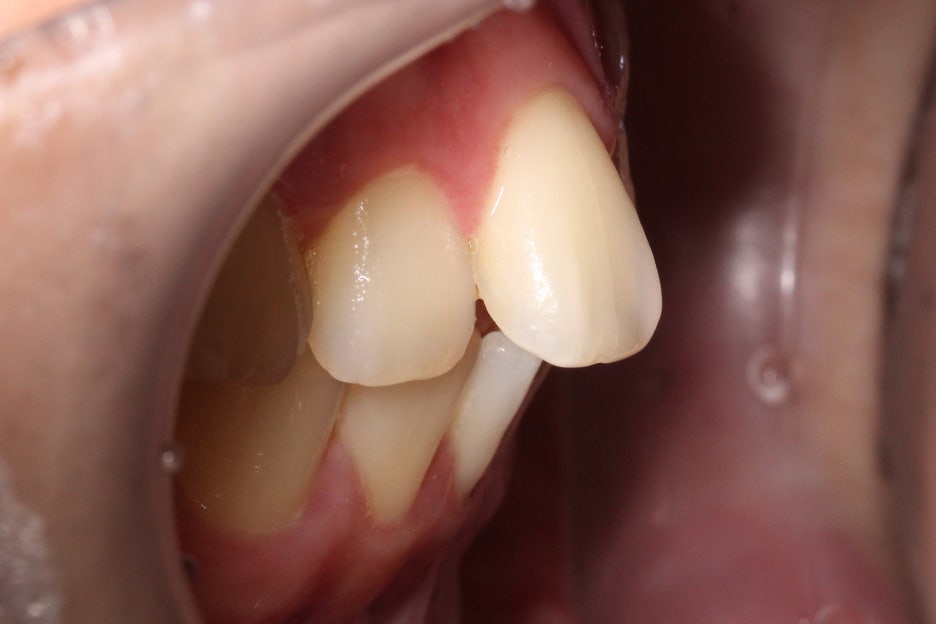

측면에서 overjet을 보면 중절치의

돌출 증상이 심한 모습으로 상악이

전방으로 뻐드러져 있어 입이 튀어나와 보이고

자꾸 입이 벌어지는 습관이 생길 수 있습니다.

좌우의 교합평면을 보면 구치부의

교합은 비교적 양호한 편으로

부정교합 증상을 크게 나타나지 않는 모습이에요.

그러나 전치부의crowding과

중절치의 뻐드러짐이 심한 상태이기 때문에

삐뚤어진 11번 중절치를 바른 각도로

교정한 후 전치부의 crowding을

해결할 수 있도록 하였습니다.